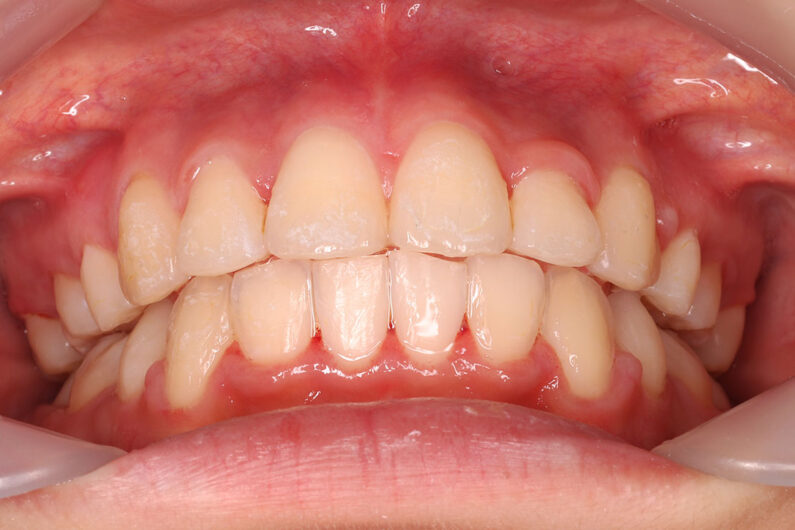

他院から紹介の患者さんです。 前歯、下の歯のガタツキをきれいにしたいということで治療を決断されました。

上顎前歯6mm、下顎前歯2.5mmの前突の状態で、口唇も前突しています。 小臼歯抜歯したスペースを使い、叢生(がたつき)と前突した前歯の後退を目標にしました。 この方も希望により、アンカースクリューは使用せず、通常の顎間ゴムで対処してもらいました。

マルチブラケット 動的治療期間 3年5か月 調整回数29回

治療後は前歯は後退し、前歯の傾斜度も良くなっています。 口唇の緊張感も改善し、エステティックラインも綺麗になりました。